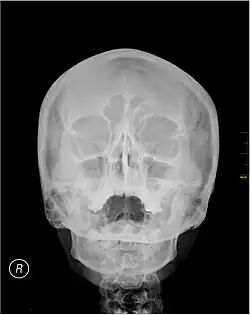

A Waters' view radiograph showing the paranasal sinuses

Waters' view (also known as the occipitomental view or parietoacanthial projection) is a radiographic view of the skull. It is commonly used to get a better view of the maxillary sinuses. An x-ray beam is angled at 45° to the orbitomeatal line. The rays pass from behind the head and are perpendicular to the radiographic plate. Another variation of the waters places the orbitomeatal line at a 37° angle to the image receptor. It is named after the American radiologist Charles Alexander Waters.

Waters' view can be used to best visualise a number of structures in the skull.

The Waters' view may not show the frontal sinus in detail.[1]